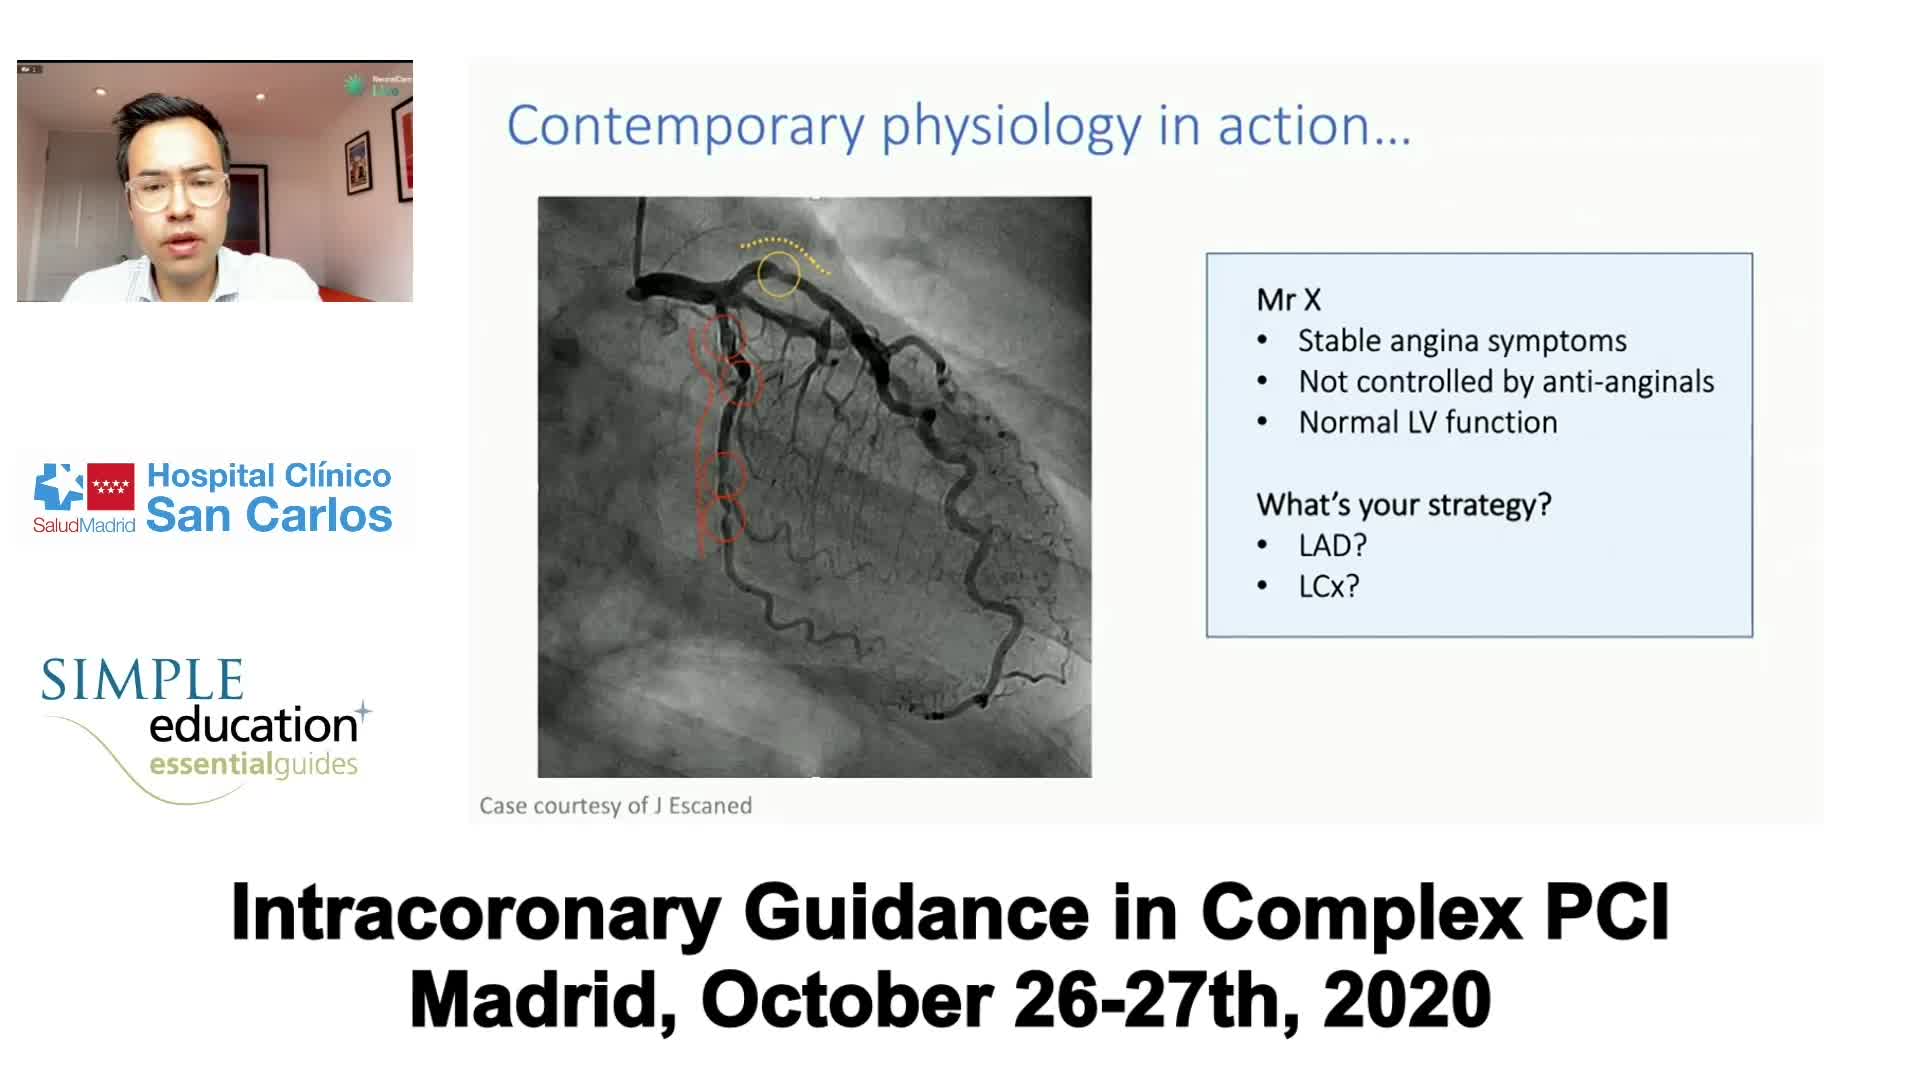

Best practices and personalised medicine in complex PCI - Prof Javier Escaned

Intracoronary guidance in acute coronary syndromes - Dr Hernan Mejia-Renteria

Coronary Bifurcations: An Update on Diagnosis, PCI planning and Imaging and PhysiologyGuidance - Dr Dejan Milasinovic